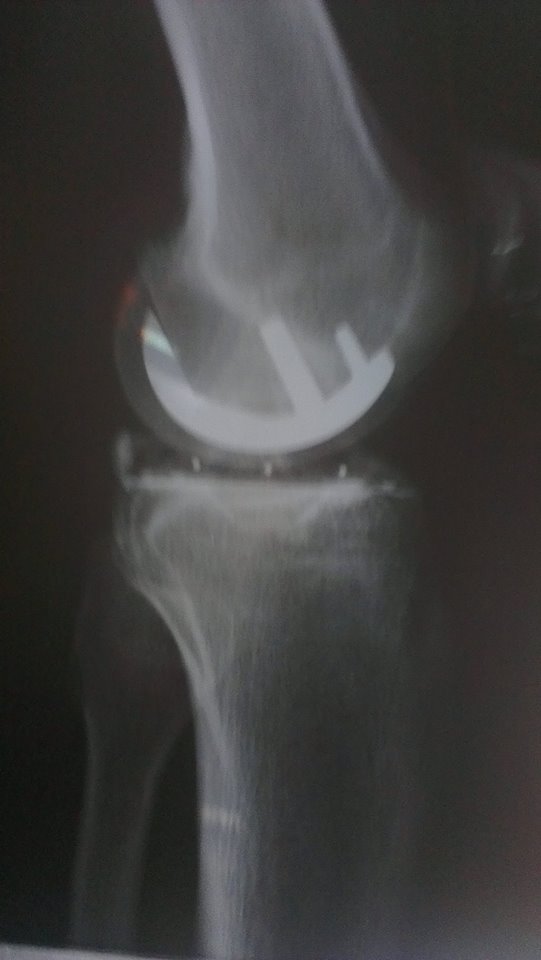

Das neue Gelenk ist drin, seit Freitagmittag bin ich zu Hause. Ein paar Schritte ganz ohne Krücken kann ich schon machen, aber ich soll langsamer machen, hat mir die nette Dame geraten die mir die Maschine zur passiven Bewegung des Beines geliefert hat.

Das sieht doch gut aus, mein teilgekoppeltes Knie ist da schon leider bedeutend aufwändiger und damit auch anfälliger.

@RazorRamon: Sorry, weiß leider nicht wie man zitiert. Bei einem teil gekoppelten Knie gibt noch einen Metallpin, der vom Oberschenkel in ein Loch der Gegenseite des Unterschenkels greift und darin beweglich ist. Das muss man machen, wenn der Bandapparat zu schwach für den Seitenhalt ist. Damit die stark einwirkenden Kräfte gehalten werden können, zahlt man einen hohen Preis dafür: Man muss die Knieprothese auf beiden Seiten mit langen Schäften verankern und entsprechend viel Knochensubstanz opfern.